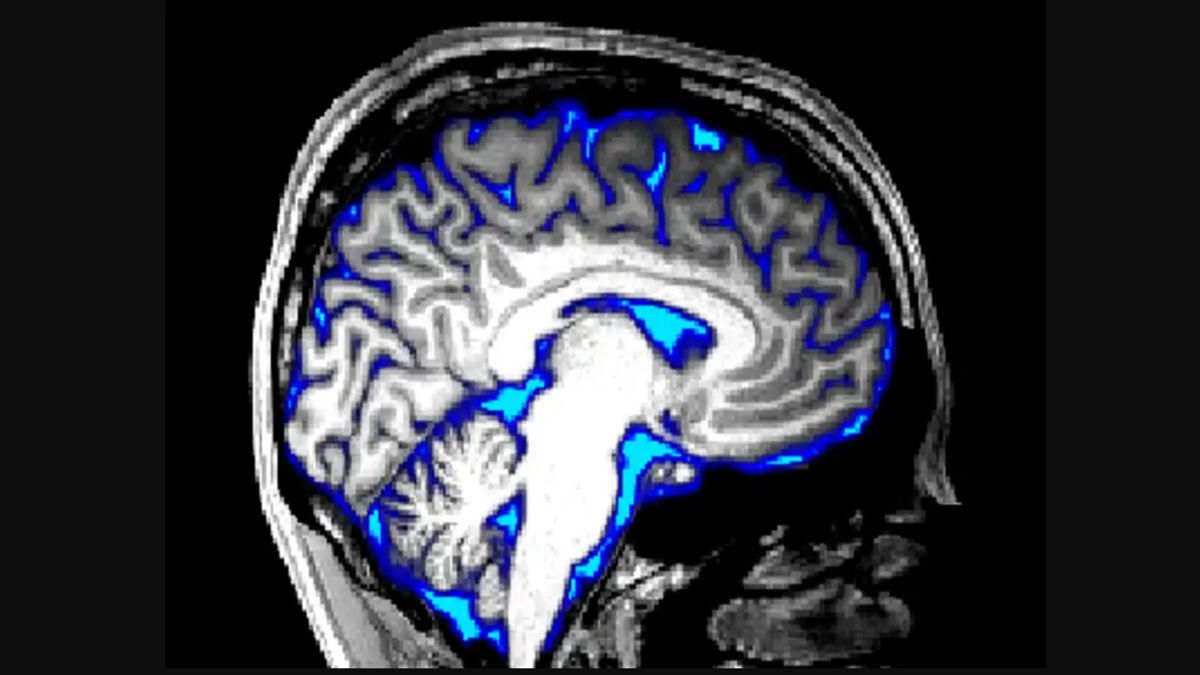

Scientists have created an artificial intelligence tool that has the potential to aid doctors in the treatment of aggressive brain tumours by identifying traits that direct surgery.

Harvard Medical School (HMS) scientists have developed this AI tool for swift DNA decoding of brain tumours during surgery.

The charm tool studies images to quickly pick out the genetic profile of a kind of tumour called glioma, a process that currently takes days or weeks, said Kun-Hsing Yu, senior author of a report released Friday in the journal Med.